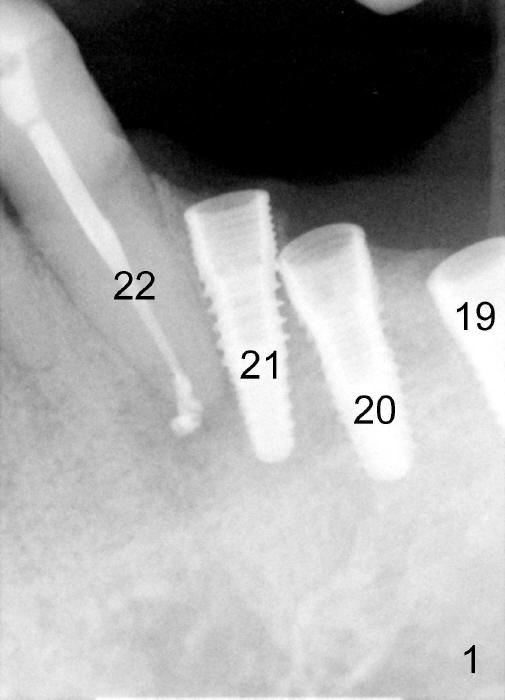

Three weeks post RCT for #22, the patient returns for implant placement at the sites of #19-21 (Fig.1,2). He is asymptomatic. But pain is not well controlled when osteotomy is being done at the site of 21. A shorter and smaller implant (4.1x12 mm, insertion torque <15 Ncm) is placed than planned (4.5x14 mm). One month postop, the implant is not stable at the site of 21 (Fig.3-5). There is a space around the implant, which is continuous with periapical radiolucency (Fig.3 arrowheads). It appears that the immediate implant should have been placed longer following RCT of the neighboring tooth. The tooth #21 has also pre-existing periapical infection.

The patient is scheduled to return 2 months postop. If there is no percussion associated with #22 and the implant at #21 remains unstable, a new PA is to be taken. The implant may be torqued down. If it does not work, the implant is removed. The socket is examined for its integrity. Deepen osteotomy for 1-2 mm and re-place the same implant. If insertion torque is low, use a larger and longer implant.